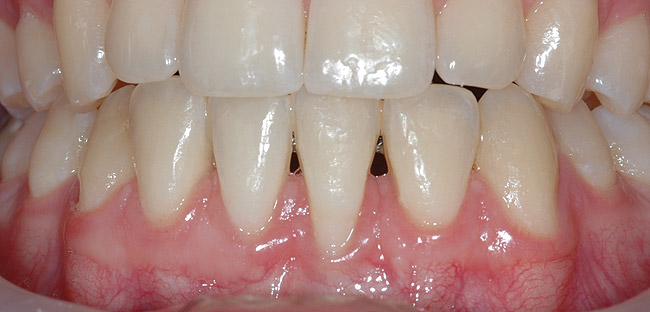

CASE 6 Fig 14. Post-orthodontic Miller Class II recession treated with a combined orthodontic-surgical approach. Clinical view 5 years after first orthodontic treatment showing GR of right lower incisor and a labially prominent root.

Figure 14

Fig 15. Same patient 2 years later showing worsening of GR and inflammation.

Figure 15

Fig 16. Occlusal view of patient shows the difference in angulation between the affected and the adjacent incisors.

Figure 16

Fig 17. Lateral view of same patient showing the root prominence.

Figure 17

Fig 18. CBCT sagittal view shows no bone on the labial aspect and 2.5 mm bone thickness on the lingual aspect.

Figure 18

Fig 19. Frontal view showing the orthodontic appliance used in same patient.

Figure 19

Fig 20. Occlusal view after second orthodontic treatment showing corrected B-L inclination.

Figure 20

Fig 21. Frontal view shows narrowing of the GR.

Figure 21

Fig 22. Frontal view of same patient 4 weeks postsurgical root coverage.

Figure 22

Fig 23. Same patient at 3-year follow-up visit showing a stable esthetic result.

Figure 23